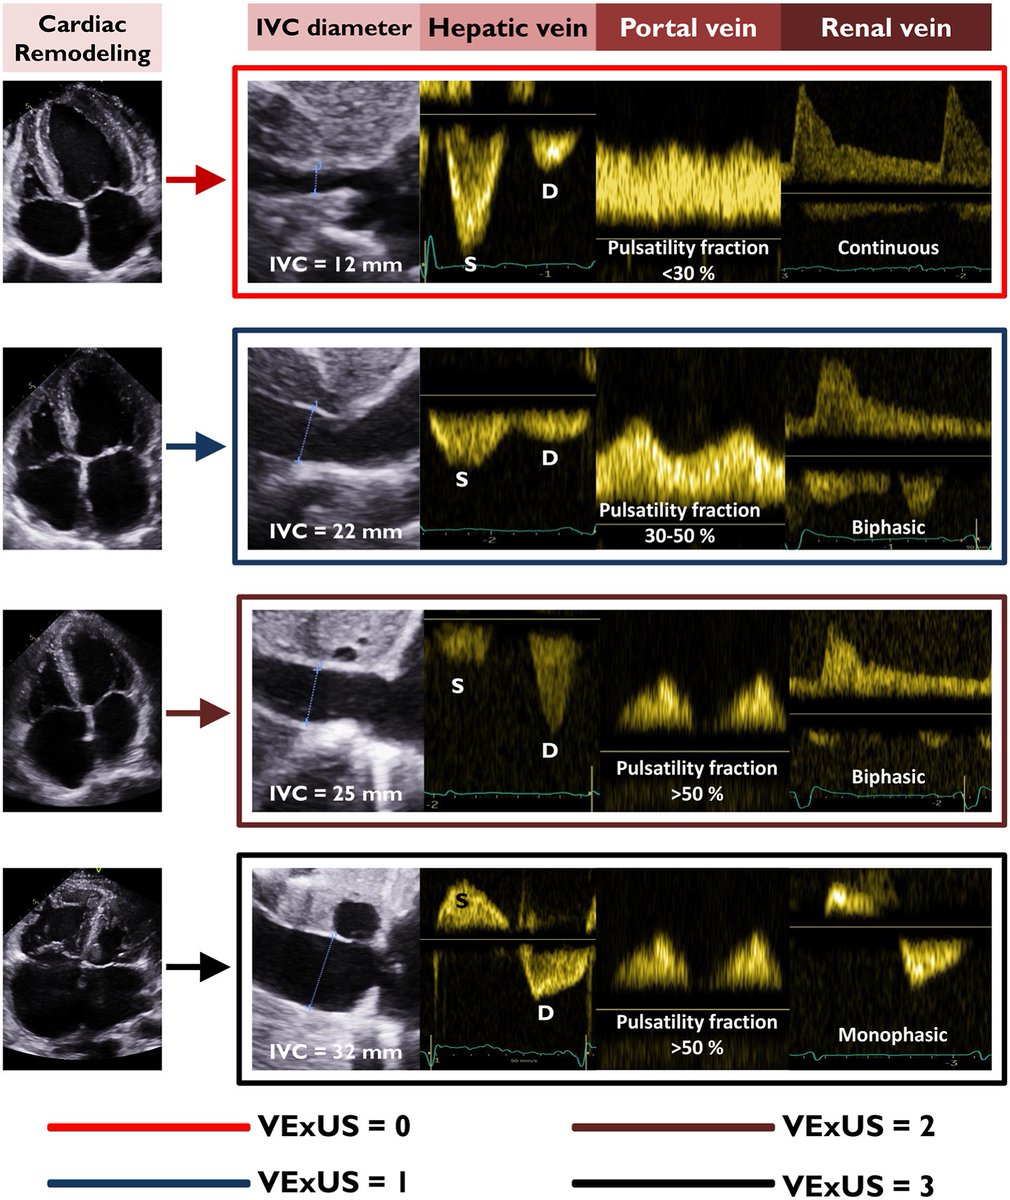

Decoding #VExUS: a practical guide for excelling in #POCUS assessment of venous congestion. - Taweevat “Games” Assavapokee & team #FOAMed #Nephpearls 🔗 theultrasoundjournal.springeropen.com/articles/10.11…

The final typeset version is out - #POCUS over Punchlines: Rethinking the #Cardiology - #Nephrology Standoff in the Era of #MedEd Humor 🔗 karger.com/crm/article/15… #Nephpearls #VExUS Eduardo R Argaiz Rafael de la Espriella Marta Cobo Marcos Gregorio Romero-González

This 2021 review on #POCUS for hemodynamic assessment, published in ASN Kidney360, remains one of the most cited on this topic (💯+). Grateful for the continued support; especially proud to have co-authored it with Nathaniel Reisinger and Eduardo R Argaiz, co-founders of IAPN, back when